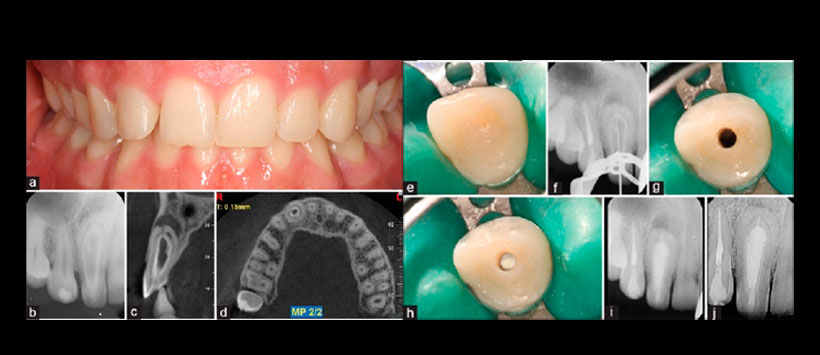

Figura 3: Tratamiento en pieza 2.2. a) Radiografía periapical preoperatoria, b) fotografía con presencia de una cúspide en garra por palatino, c) radiografía que muestra la eliminación del dens en el tercio coronal, d) radiografía que muestra la eliminación del dens en el tercio medio, e) radiografía que muestra la eliminación del dens en el tercio apical, f) radiografía que muestra la eliminación completa de los tejidos invaginados, g) Foto de la colocación de la barrera apical con ProRoot MTA, h) radiografía que muestra la obturación del MTA, i) radiografía que muestra la obturación con postes de fibra, j) control a los 12 meses.